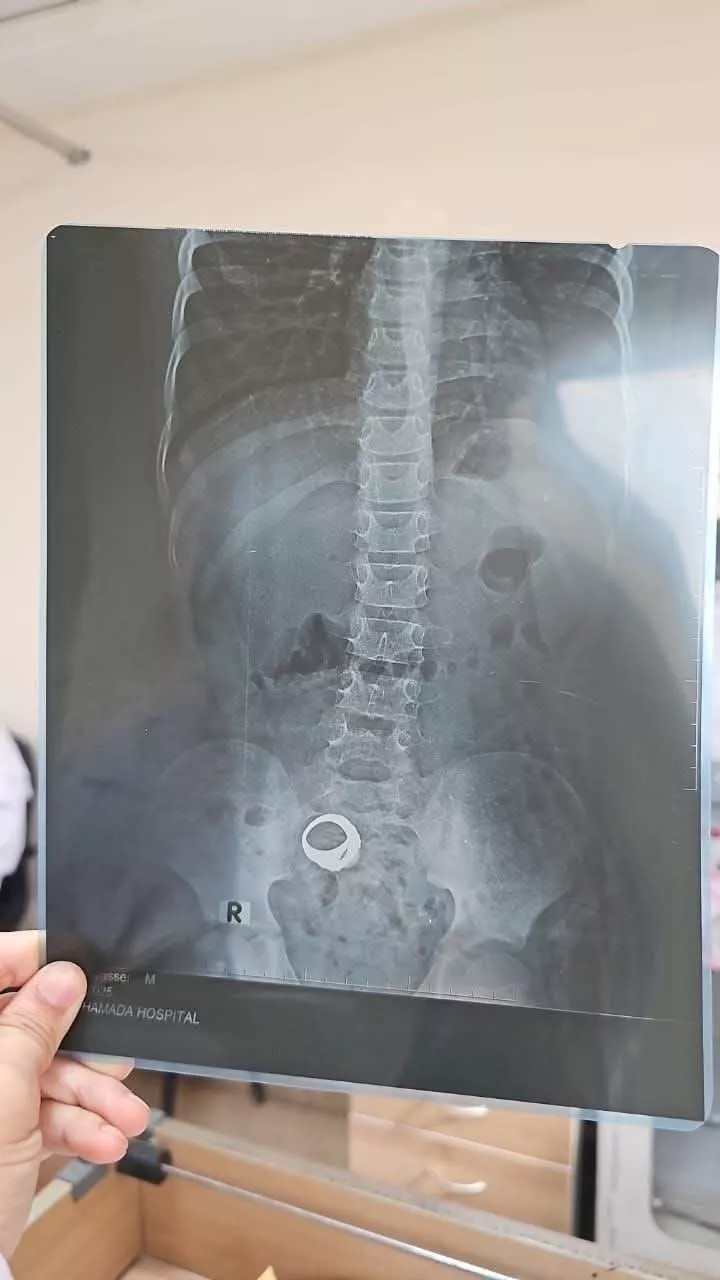

صورة الأشعة

في واقعة أعادت إلى الأذهان قصة فيلم "حياة أو موت"، ضجت مواقع التواصل الاجتماعي بمناشدات للبحث عن طفل غادر مستشفى كوم حمادة العام بالبحيرة، بعدما كشفت أشعة أُجريت له عن وجود خاتم داخل أمعائه، دون أن تعلم أسرته بالنتيجة.

بدأت القصة عندما توجهت والدة الطفل، معاذ عمار ياسر، إلى المستشفى لعلاج ابنها من مغص شديد، وبعد الكشف عليه طلب الأطباء إجراء أشعة.

وبحسب بيان المستشفى، نفذت الأم الطلب لكنها تركت نتيجة الأشعة وغادرت دون العودة للطبيب لاستكمال المتابعة، ما أثار قلق رواد "فيسبوك" الذين تداولوا صورة الأشعة مطالبين بسرعة العثور على الطفل.